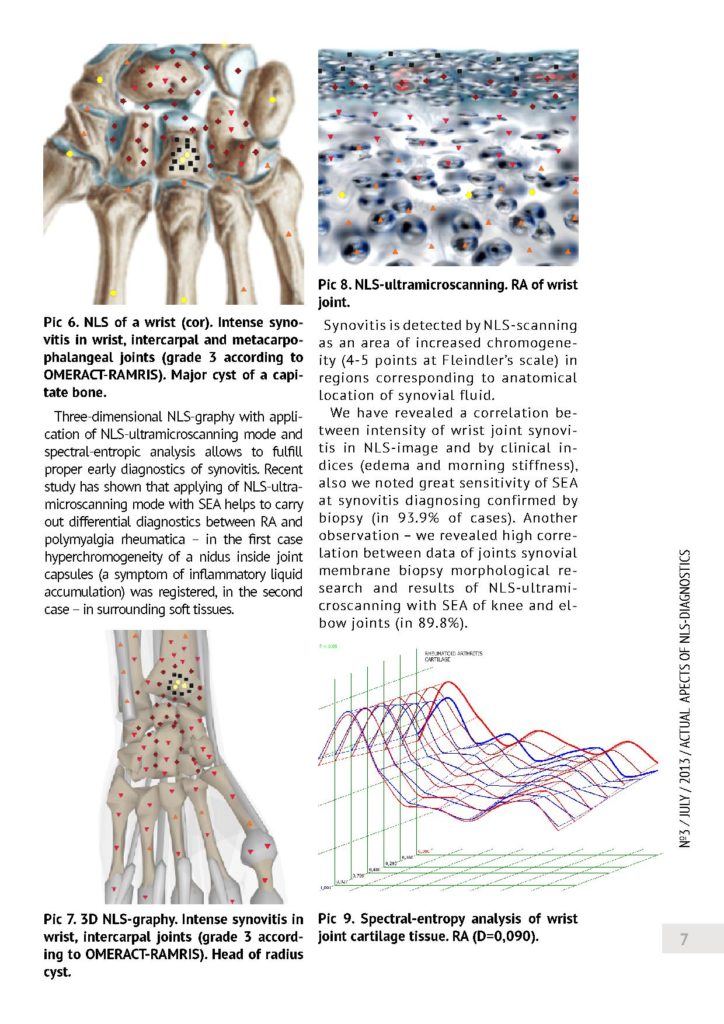

Trójwymiarowy NLS - w diagnostyce wczesnego reumatoidalnego zapalenia stawów